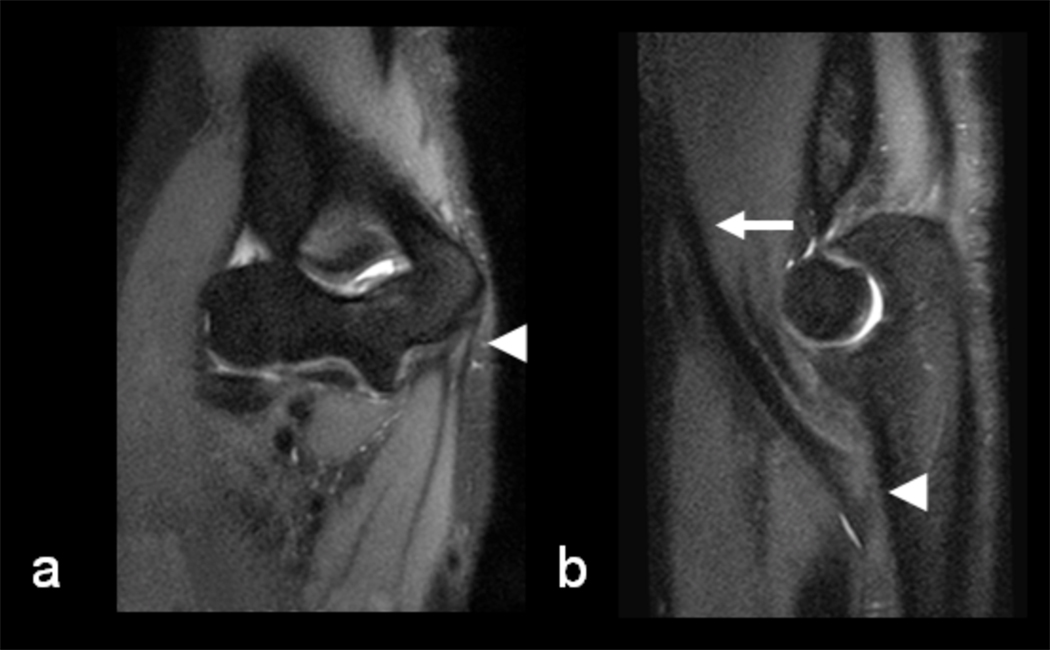

Figure 6.

47 year old male patient with surgically confirmed labral tear and full thickness cartilage lesions on the anterior superior femoral head and acetabulum who was imaged at 3.0T. (a) Sagittal fat saturated two-dimensional T1-weighted fast spin-echo image and (b) corresponding sagittal IDEAL-SPGR image (0.9 mm isotropic resolution with 6 minute scan time) of the hip show an anterior superior labral tear (arrowheads) and full-thickness cartilage lesions on the anterior superior femoral head and acetabulum (arrows). (c) Coronal fat saturated two-dimensional T1-weighted fast spin-echo image and (b) corresponding coronal IDEAL-SPGR reformat image (0.9 mm isotropic resolution with 6 minute scan time) of the hip show an anterior superior labral tear (arrowheads) and full-thickness cartilage lesions on the anterior superior femoral head and acetabulum (arrows).